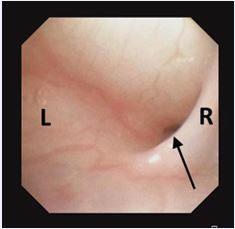

Flexible endoscopy confirmed the sinus tract, aided by visualization of a characteristic mucosal fold (Figure 2).

Figure 2 Flexible endoscopy showing an internal opening in the left pyriform sinus. A mucosal fold medial to the opening (arrow) helped localize the tract.

Most reported cases are left-sided [9-17], likely due to embryological and vascular asymmetry, including the longer course of the left tract and its descent below the aortic arch [3]. Clinically, a fourth branchial cleft sinus should be suspected in children with recurrent neck infections or episodes resembling suppurative thyroiditis. Misdiagnosis may lead to unnecessary procedures such as thyroidectomy, which does not address the underlying cause [17]. Our series demonstrates that flexible laryngoscopy, combined with gentle oxygen insufflation, can reliably identify the internal tract opening, obviating the need for rigid laryngoscopy. Flexible laryngoscopy offers several advantages, including wide availability, reduced need for general anesthesia, and avoidance of radiation exposure. This is especially valuable in pediatric patients, in whom anatomical constraints make rigid laryngoscopy more challenging and less sensitive [17]. We suggest that insufflation assists in dilating the sinus opening, improving visualization of characteristic features such as the mucosal fold or “flange” medial to the sinus opening and lateral to the upper esophageal sphincter, an anatomical landmark rarely mentioned in the literature [10-11] (Figure 2). Notably, we report for the first time a double-lumen pyriform sinus opening (Figure 7), potentially representing an anatomical variant. Flexible endoscopy may also reduce the need for imaging, particularly CT scans, which involve radiation. Ultrasound, a radiation-free modality, can aid in identifying abscesses or thyroid involvement and serve as an adjunct in evaluation, and waive the need for additional unwarranted imaging as CT.